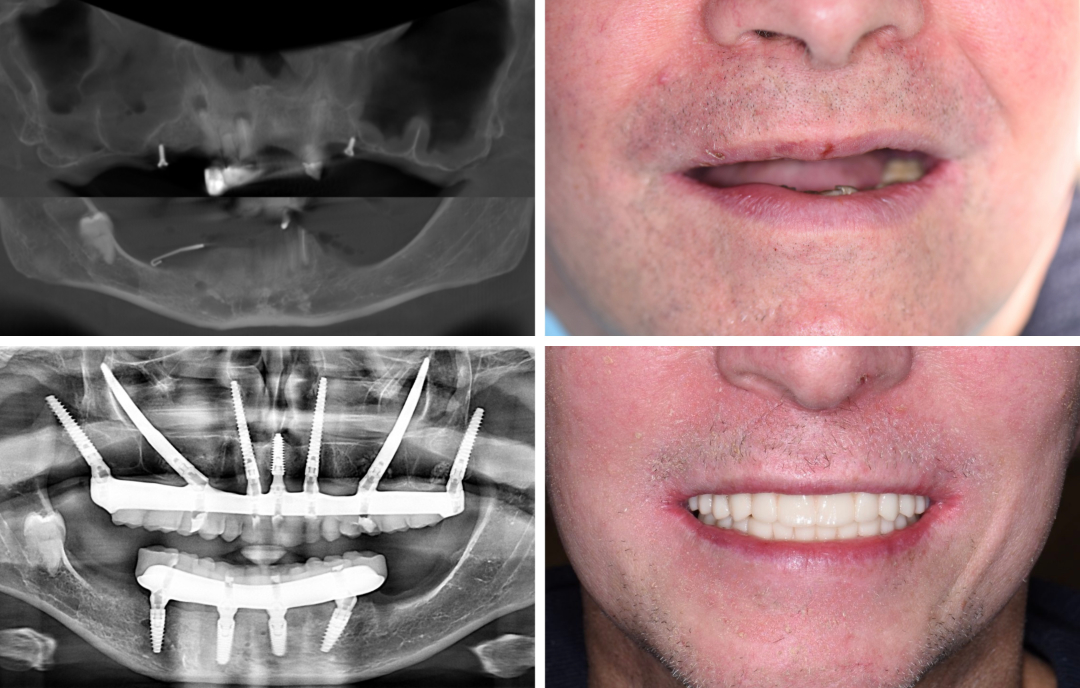

Der 37-jährige Patient hatte aufgrund seiner Grunderkrankung alle Zähne verloren, und im Unterkiefer waren sämtliche verbliebene Zähne nicht erhaltungswürdig.

In einer ITN-Operation wurden die nicht erhaltungswürdigen Zähne entfernt. Anschließend wurde mittels navigierter Full-Arch-Rekonstruktion eine direkte, provisorische Sofortversorgung ermöglicht.

Die navigierte Full-Arch-Rekonstruktion gibt vielen Patienten Hoffnung auf festen Zahnersatz und ermöglicht eine Rückkehr zu verbesserter Lebensqualität.